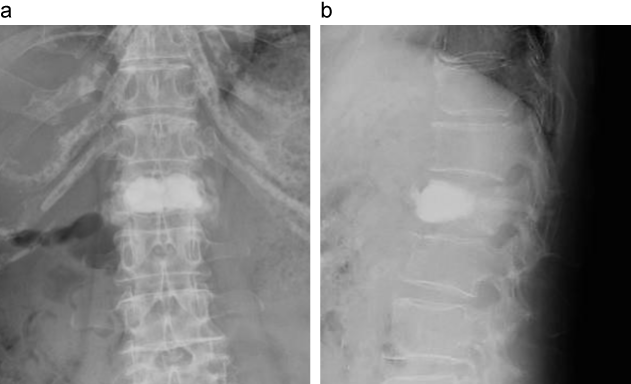

症例2のX線機能撮影

第1腰椎に椎体骨折を認める。前後屈の機能撮影において、第1腰椎に異常な可動性を認め、骨癒合不全を認める。

a:正面像

b:立位前屈像

c:仰臥位側面像